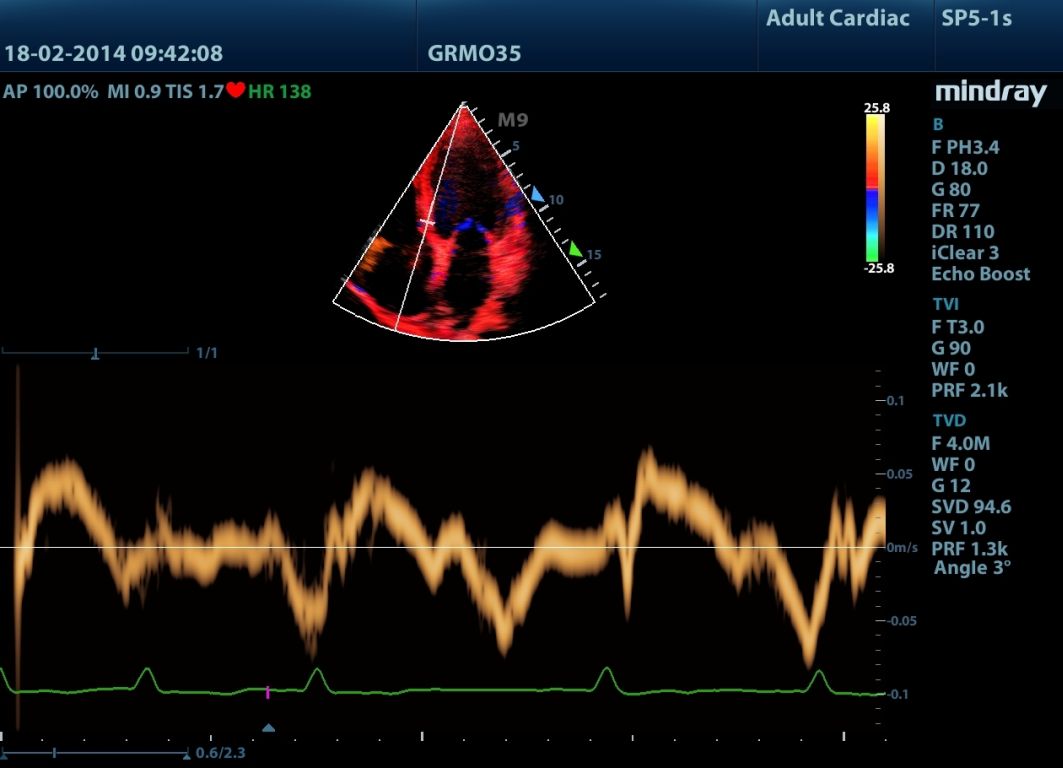

Mindray M9 je dopplerovský ultra ľahký prenosný UZV prístroj najvyššej High End triedy s použitím single crystal 3T sond (vynikajúce zobrazenie blízkeho i vzdialeného poľa), HDR FLOW, ECHO BOOST, Natural Touch Elastography, kontrastného zobrazenia, TDI. Špeciál hlavne pre kardiológiu.

Klinické obrázky:

- Echo Boost (unikátny patentovaný signál procesor s inteligentnou echo detekciou na zvýraznenie jemných štruktúr myokardu a endokardu)